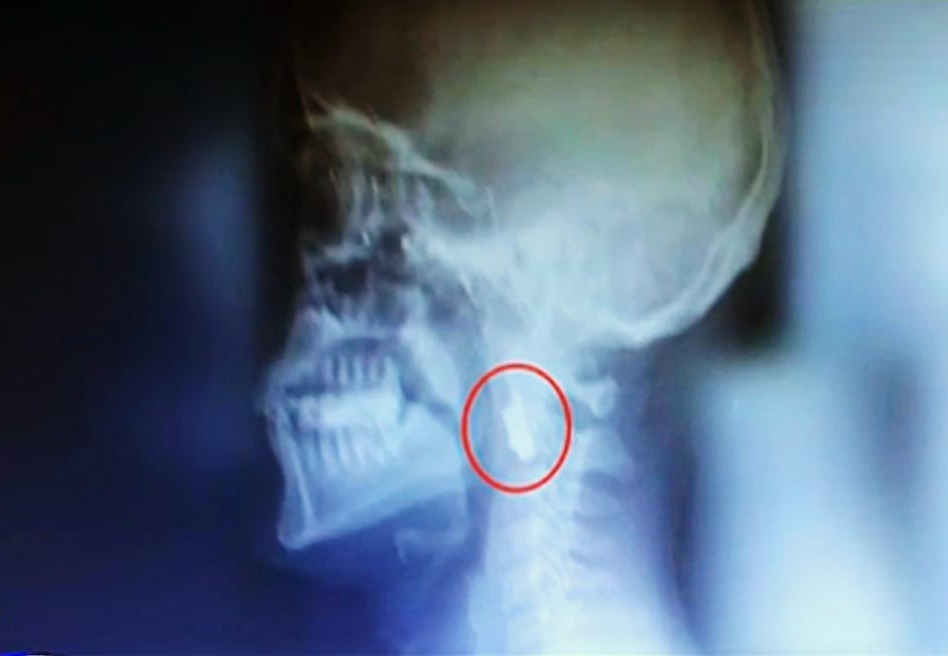

15 Temmuz hain darbe girişiminde vatanı için sokağa çıkan 2 çocuk babası 39 yaşındaki İsmail Acur tam sağ gözünden vuruldu. G3 mermisi gözünden girdi şahdamarına değdikten sonra durdu. 7 yıldır o G3 mermisi ile yaşayan gazi İsmail Acur; "O gece bir gözümü vatanıma feda ettim. O kurşunu şah damarımda her hissettiğimde hainlerin bana yaşattığı milletimize yaşattığı geceyi tekrar tekrar hatırlıyorum" ifadelerini kullandı.

15 Temmuz gecesi hain darbe girişiminde, darbecilere karşı en ön safta direnenlerden gazi İsmail Acur (39) 7 yıldır vücudunda duran G3 mermisi ile yaşıyor.

O gece İBB'nin Saraçhane'deki binasının önünde başından vurulan ve sağ gözünü kaybeden Acur'un ise kurşun tam şah damarının yanına saplandı.

7 yıldır gecesi gündüzü şah damarındaki G3 mermisi ile geçiyor. Tüm X-Ray cihazlarından geçerken illa bir uyarı alıyorum diyen Acur o artık bizim için ahirete götüreceğimiz bir madalya. Şehitlik bana şah damarım kadar yakın diyor.

Acur " 15 Temmuz hain darbe girişimi üzerinden 7 sene geçti bana halen dün gibi geliyor. O gece bir gözümü vatanıma feda ettim ve ömür boyu gözümden giren kurşun boynumda benimle birlikte mezara girecek. Bu süreçte çok sıkıntılar çektim uykusuz gecelerim çok oldu ölüm riski olduğu için kurşuna müdahale edemiyorlar.